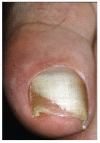

Onychomycosis is the most common nail infective disorder. It is caused mainly by anthropophilic dermatophytes, in particular by Trichophyton rubrum and T. mentagrophytes var. interdigitale. Yeasts, like Candida albicans and C. parapsilosis, and molds, like Aspergillus spp., represent the second cause of onychomycosis. The clinical suspect of onychomycosis should be confirmed my mycology. Onychoscopy is a new method that can help the physician, as in onychomycosis, it shows a typical fringed proximal margin. Treatment is chosen depending on the modality of nail invasion, fungus species and the number of affected nails. Oral treatments are often limited by drug interactions, while topical antifungal lacquers have less efficacy. A combination of both oral and systemic treatment is often the best choice.